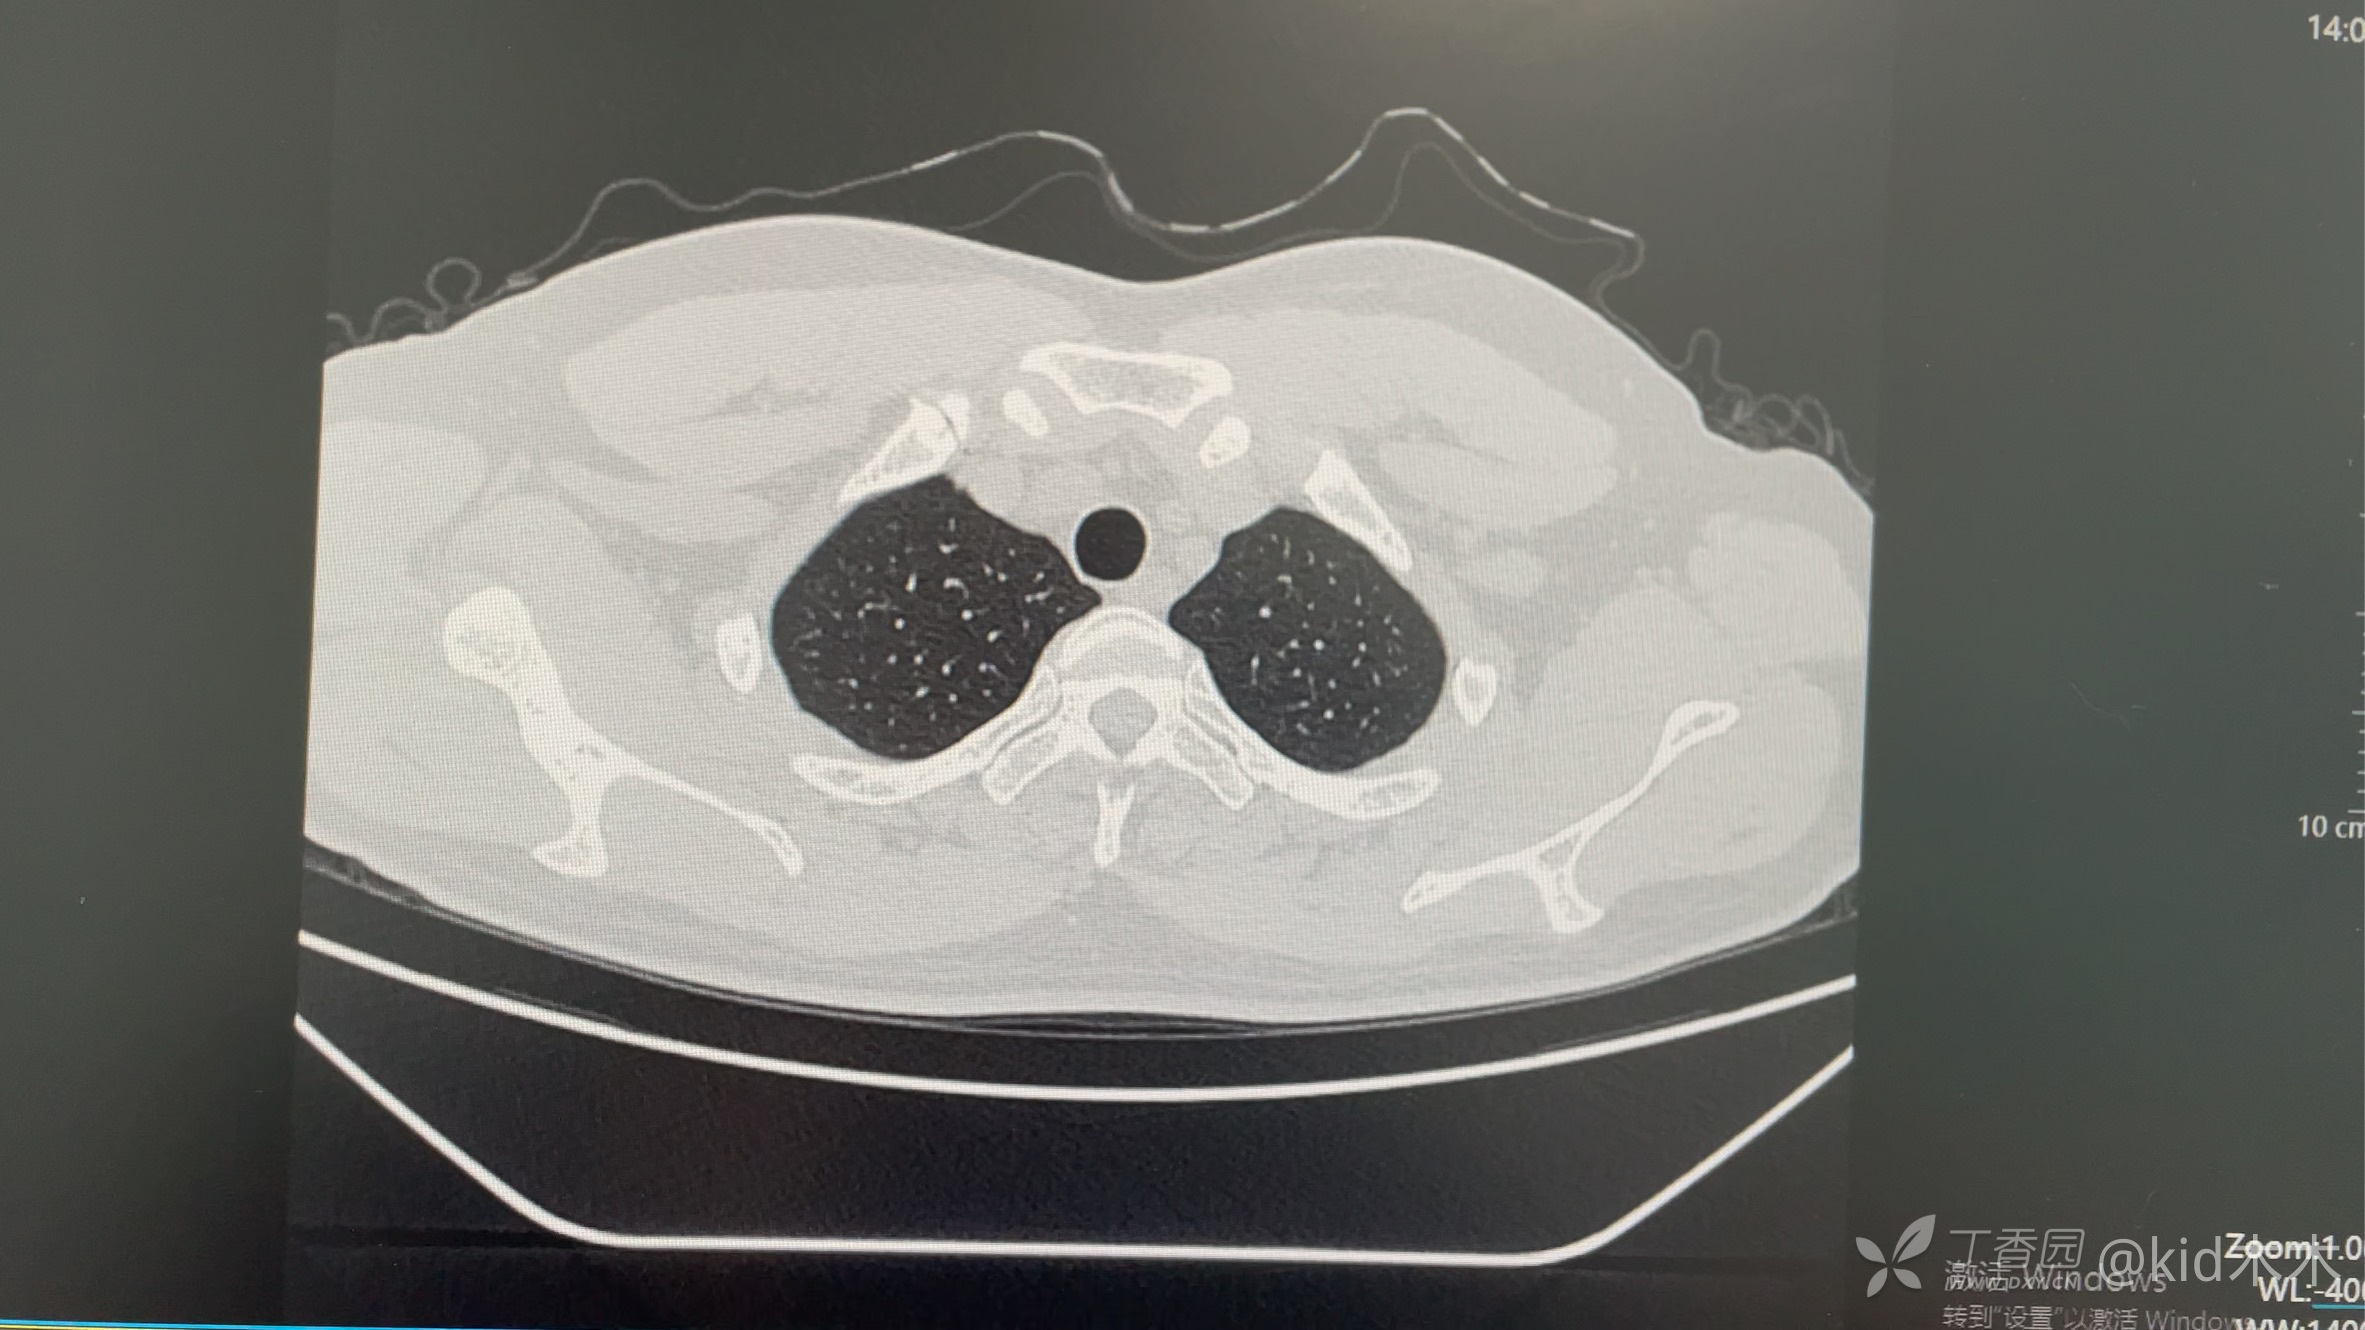

1.13体检发现右肺结节,3个月后复查(4.19)右肺下叶感染病灶,期间未治疗,无症状。没有接触小动物,无既往史,查血肿瘤标志物,血生化,血常规,凝血功能,输血八项,抗酸染色,G试验➕GM试验无异常。结核杆菌y干扰素结果30.8,ppd试验强阳性。现阶段考虑真菌感染,口服伊曲康唑3天。